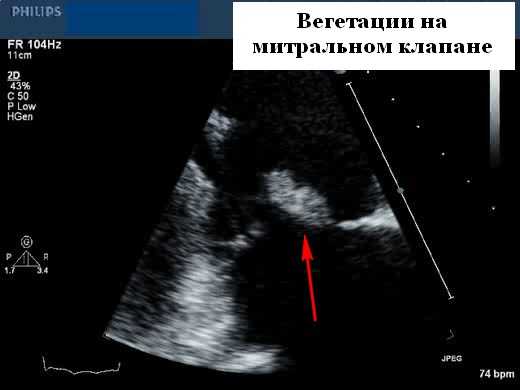

- Вегетации (подвижные образования на клапане, движутся в сердечном цикле, но их часто трудно увидеть)

- M-режим может отображать вегетации в виде нескольких толстых эхо-линий, наложенных на M-режим протеза, но и M-режим, и 2D-эхокардиография могут быть затруднены из-за реверберации и маскировки. Небольшие вегетации (

Вегетации имеют ряд типичных эхокардиографических характеристик, и диагноз обычно может быть установлен с относительно высокой степенью уверенности с помощью эхокардиографии в сочетании с клинической симптоматикой. Они кажутся менее отражающими (серыми) по сравнению с нормальной тканью клапана и расположены перед клапаном на линии струи регургитации (предсердная поверхность митрального клапана и поверхность желудочков створок аорты). Обычно они выглядят дольчатыми с неровными, плохо очерченными границами и имеют хаотическое движение, в отличие от других клапанных образований (фиброэластомы и т. д.), которые имеют тенденцию к более высокому отражению, с четко определенными границами и менее хаотичным движением. Тонкие протяженные клапанные прикрепления с узким основанием, скорее всего, будут неинфекционными фибринозными нитями, чем вегетациями. Признаки, которые помогают отличить вегетации от других образований, включают наличие разрушения створки, регургитации клапана и образования абсцесса или свища. Сообщается, что чувствительность трансторакальной эхокардиографии для выявления признаков эндокардита составляет от 44 до 60%, по сравнению с чувствительностью 88 и 100% для ЧПЭхоКГ. Мелкие вегетации ( 90%), хотя при более высоком разрешении чреспищеводной эхокардиографии повышенная чувствительность может происходить за счет немного сниженной специфичности (возможность маркировать небольшие доброкачественные фибринозные тяжи на нативных и протезных клапанах или незначительно подвижные шовный материал на протезах клапанов в виде мелких нитей).